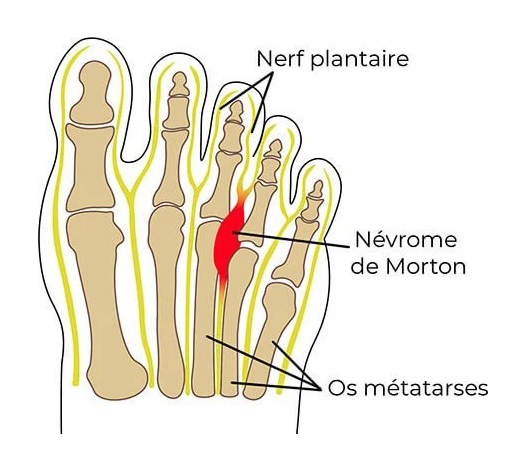

Névrome de Morton

Il s’agit de la compression d’un nerf interdigital entre deux têtes métatarsiennes. Le névrome se situe le plus souvent entre le 3e et 4e métatarsien.

Les phénomènes de compression nerveuse déclenchent des douleurs aiguës neurologiques plantaires, entre les orteils, qui peuvent remonter vers la cheville. Les douleurs sont généralement déclenchées par la marche, la station debout prolongée et le port de chaussures serrées.